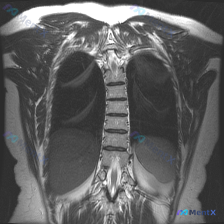

整理到一个很有意思的影像读片材料: 一张胸部MRI-T2序列冠状位影像,原始的影像学分析写的是“胸廓、脊柱、纵隔及肺野解剖结构基本正常,未见明显的病理性高信号改变”,甚至明确提了“椎体信号均匀,骨皮质轮廓清晰,未见明显骨质破坏”。 但拿到这份材料的人,第一眼观察到的线索是——脊柱侧弯(Scolios...

整理到一份临床诉求指向「脊柱侧弯」的病例资料: 仅有的影像检查是胸部MRI冠状位T2加权像,影像报告的核心发现是: - 双侧肺野、纵隔、心影未见明显局灶性病变或占位; - 胸椎序列清晰,椎体形态基本正常,未见明显的形态异常或骨质信号改变; - 双侧胸廓、软组织结构大致对称。 但结合「脊柱侧弯」的核心...

整理到一个挺有意思的病例复盘点,想跟大家讨论下临床思维: - 核心场景:患者主诉“脊柱侧弯”,但拿到的一张胸部冠状位T2 MRI报告里写着「胸椎序列排列整齐,左右基本对称,未见明显异常」。 - 影像背景:图像清晰度良好,胸廓、肺野、上腹部显露部分确实没看到积液、肿块或骨髓水肿信号。 问题来了:这种主...